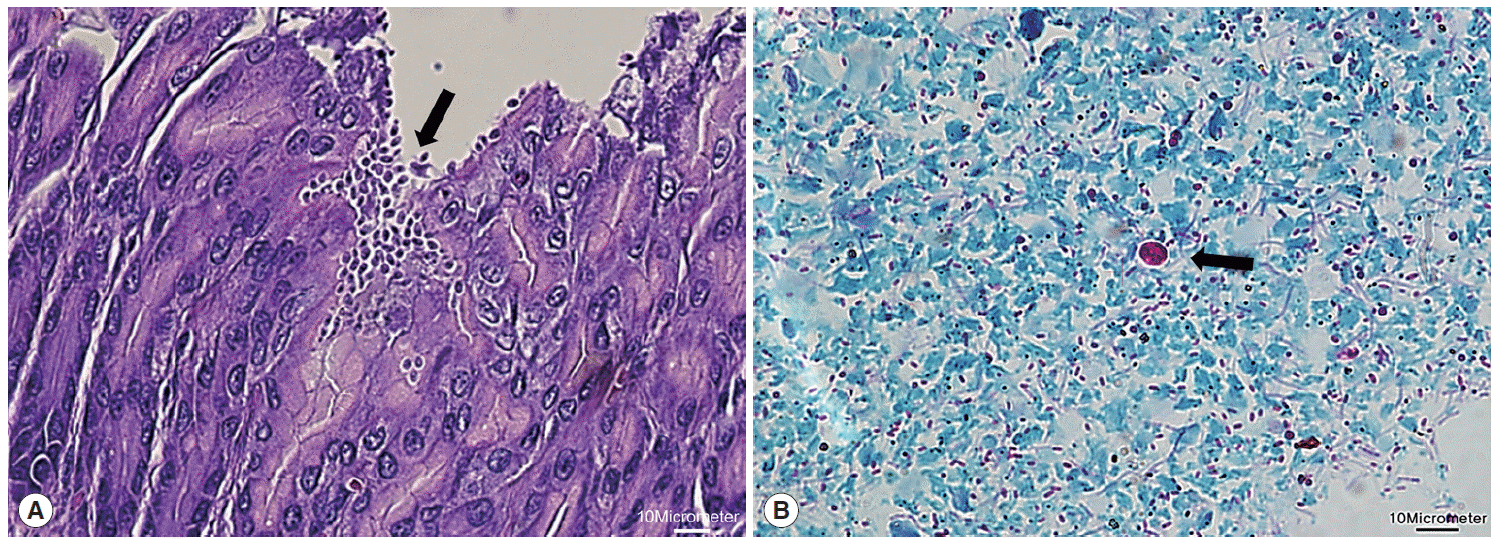

Detection and Molecular Characterization of Cryptosporidium spp. from Wild Rodents and Insectivores in South Korea

The Korean Journal of Parasitology 2015;53(6):737-743.